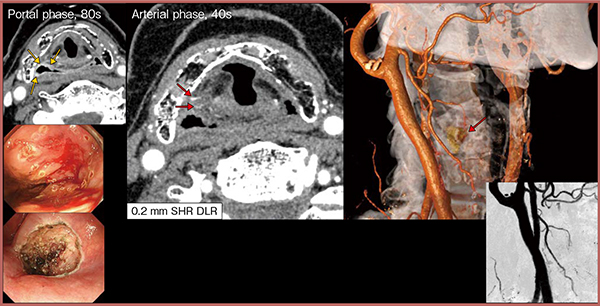

図2は,下咽頭早期がんの内視鏡手術前の血管評価の画像であるが,PCD-CTの高分解能画像にDLRを併用することで,腫瘍に向かう微細な血管の走行(→)まで描出可能である。

図2 PCD-CT(SHR+DLR)による下咽頭早期がんの内視鏡手術前の血管評価

→:下咽頭表在がん →:微細な血管